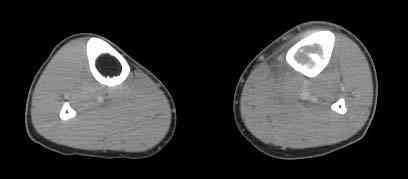

важаемые коллеги! Поступил больной 22 лет. Болен с января 2006 - появились боли в области верхнейтрети голени. При первичном осмотре в поликлинике был заподозрен первично-хронический остеомиелит - осмотрен гнойным хирургом - произведена биосия . Заключение - хондросаркома. Осмотрен онкологом - с учетом характера опухоли - химиотерапия, лучевое лечение не показано. Предложена либо ампутация, либо решение вопроса о возможности выполнения органосохраняющей операции. При обращении к нам произведена сцинтиграфия скелета - зоны гиперфиксации РФП: верхняя треть голени- 960%, нижняя треть бедра - 380%, Дистальный метафиз голени и затылочная область - 140%. В легких - метастазов нет. Произведена КТ (картинки в приложении). Учитывая абсолютную нестыковку рентгенологических и морфологических данных повторно биопсия. Выявлено, что первичная биопсия выполнялась из поверхностной параоссальной зоны - там локализованы хрящеподобные массы, далее очень плотная кость без хрящевых участков - биоптат взят фрезой с большим трудом. Морфологического заключения пока нет. Хотелось бы узнать Ваши варианты диагноза и соответственно тактику.

Диагноз можно подтвердить дополнительными исследованиями, КТ грудной клетки или Магнето Резонансовые Исследования или также можно подтвердить во время операции экспресс биопсией совместно с паталогоанатомом.

Если диагноз подтвержден до операции, рекомендуется предварительная химиотерапия, из хирургических лечении здесь много вариантов, включая ампутацию, костную аутопластику и ротационную органосохранную пластику.